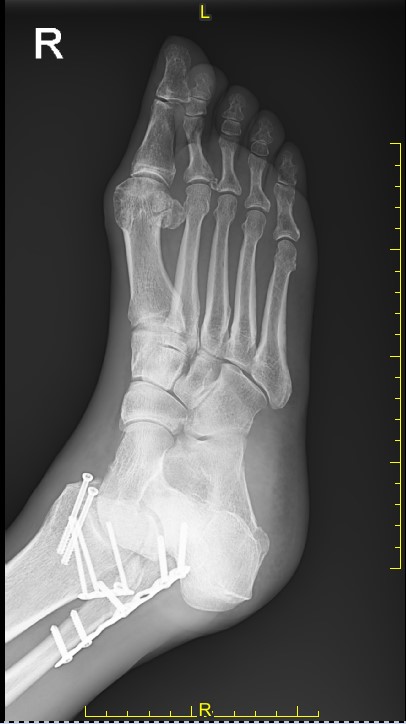

I fell and broke my ankle while roller skating in Central Park. Fortunately, I was taken to HSS at NYP, where I received outstanding care at all levels. Dr. Behrens did surgery for three broken bones in my ankle, and everything went well. Now, eight months later, I am doing everything like before - going up and down the stairs, working out at the gym, and doing the Limbo!

Steve B. Behrens, MD

Foot and Ankle, Sports Medicine, and Trauma Surgeon